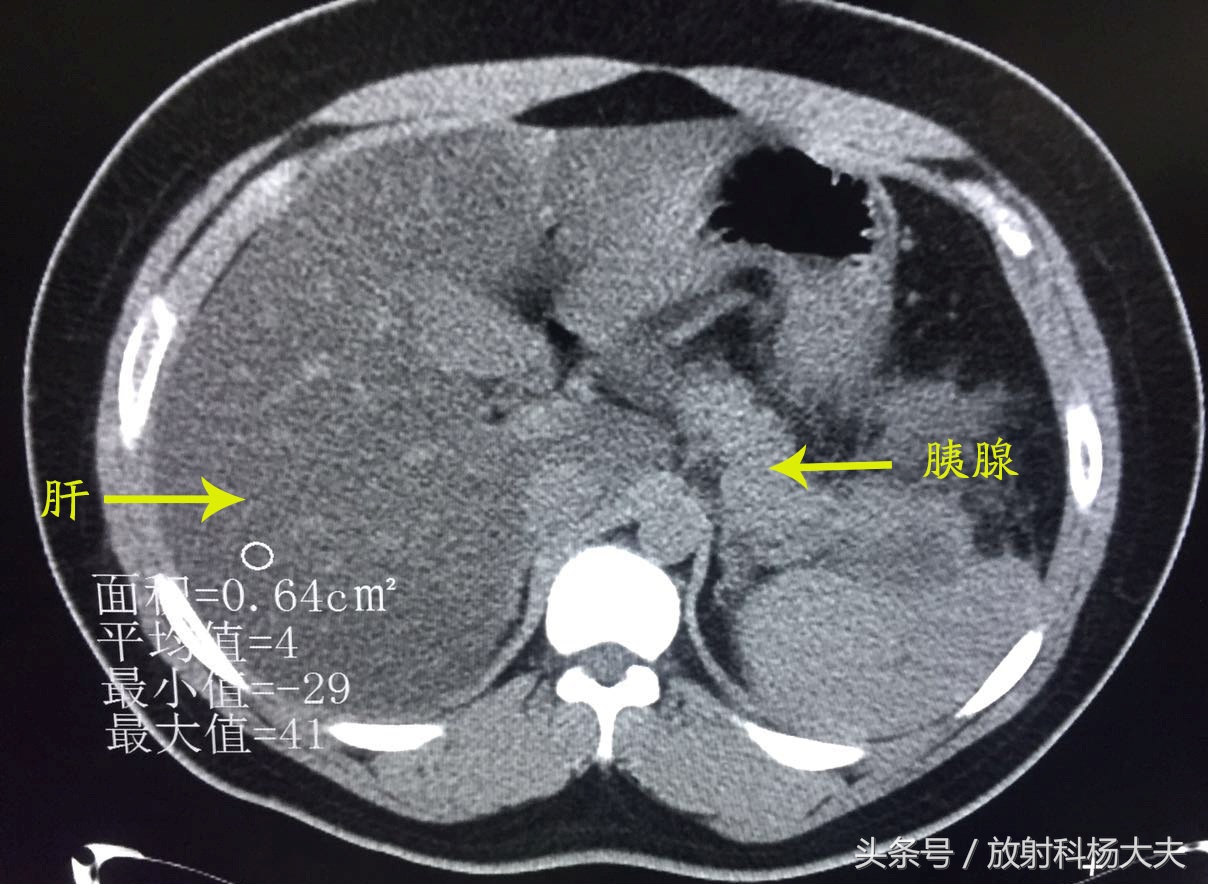

放射科的急诊总是会遇见各种急患,外伤的、头晕头痛的、恶心呕吐的、腹痛难耐的...前几天夜班来了一位身材略胖的小伙子,29岁,由于跟朋友进食火锅后突发上腹疼痛就诊,左上腹为著,为持续性胀痛,疼痛不可耐受,并向后背部放射,无肩部放射痛,疼痛不因体位变化而缓解,伴寒战、发热、大汗。做了CT,其图像如下所示:

可发现肝脏密度明显弥漫性减低,且明显低于同层面脾脏密度。胰腺周围可见渗出改变。腹痛原因找到了----急性胰腺炎伴重度脂肪肝,可这肝脏密度也太低了。